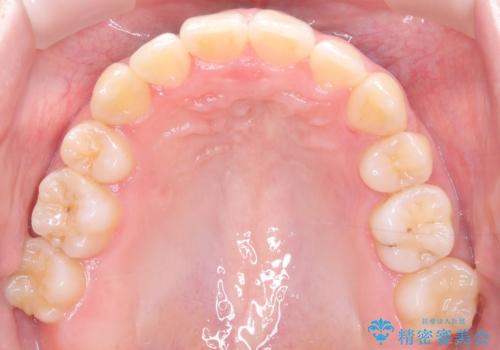

- 患者様は、結婚式までに歯並びを整えたいとのご要望で来院されました。診断の結果、上下左右の第一小臼歯を抜歯し、歯列全体を整える計画としました。審美性を重視し、目立ちにくいホワイトワイヤーを使用した矯正を提案しました。治療期間は2年を目安とし、結婚式までに前歯の整列と噛み合わせを優先的に整えるスケジュールで進めました。定期的な調整と経過観察を通じて、計画的に治療を進めました。

結婚式までに仕上げるため、通常よりも細かく調整を行い、歯の動きを効率的に管理しました。審美ワイヤーを使用したことで、治療中も目立ちにくく、写真撮影などの日常生活での見た目の負担を軽減しました。抜歯部分のスペースを閉じる際には、前歯の位置や噛み合わせのバランスに配慮し、過度な力がかからないよう進めました。患者様の大切なイベントに間に合うよう治療計画を立て、理想的な仕上がりを実現しました。